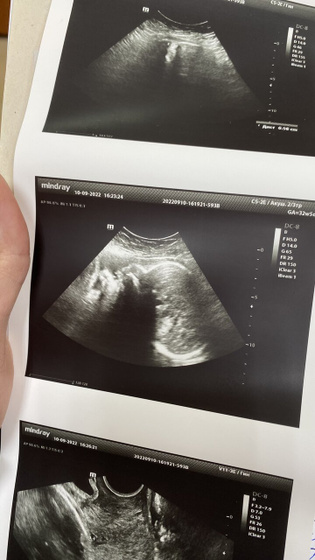

Сегодня наконец были на узи.

У нашей женщины все хорошо

Кровотоки хорошие.

Шейка у меня 30мм (для срока вроде как норм)

Воды 14 индекс (вроде там в см измеряется )

Вес 2138 ?гр. я думаю вполне нормально ??)